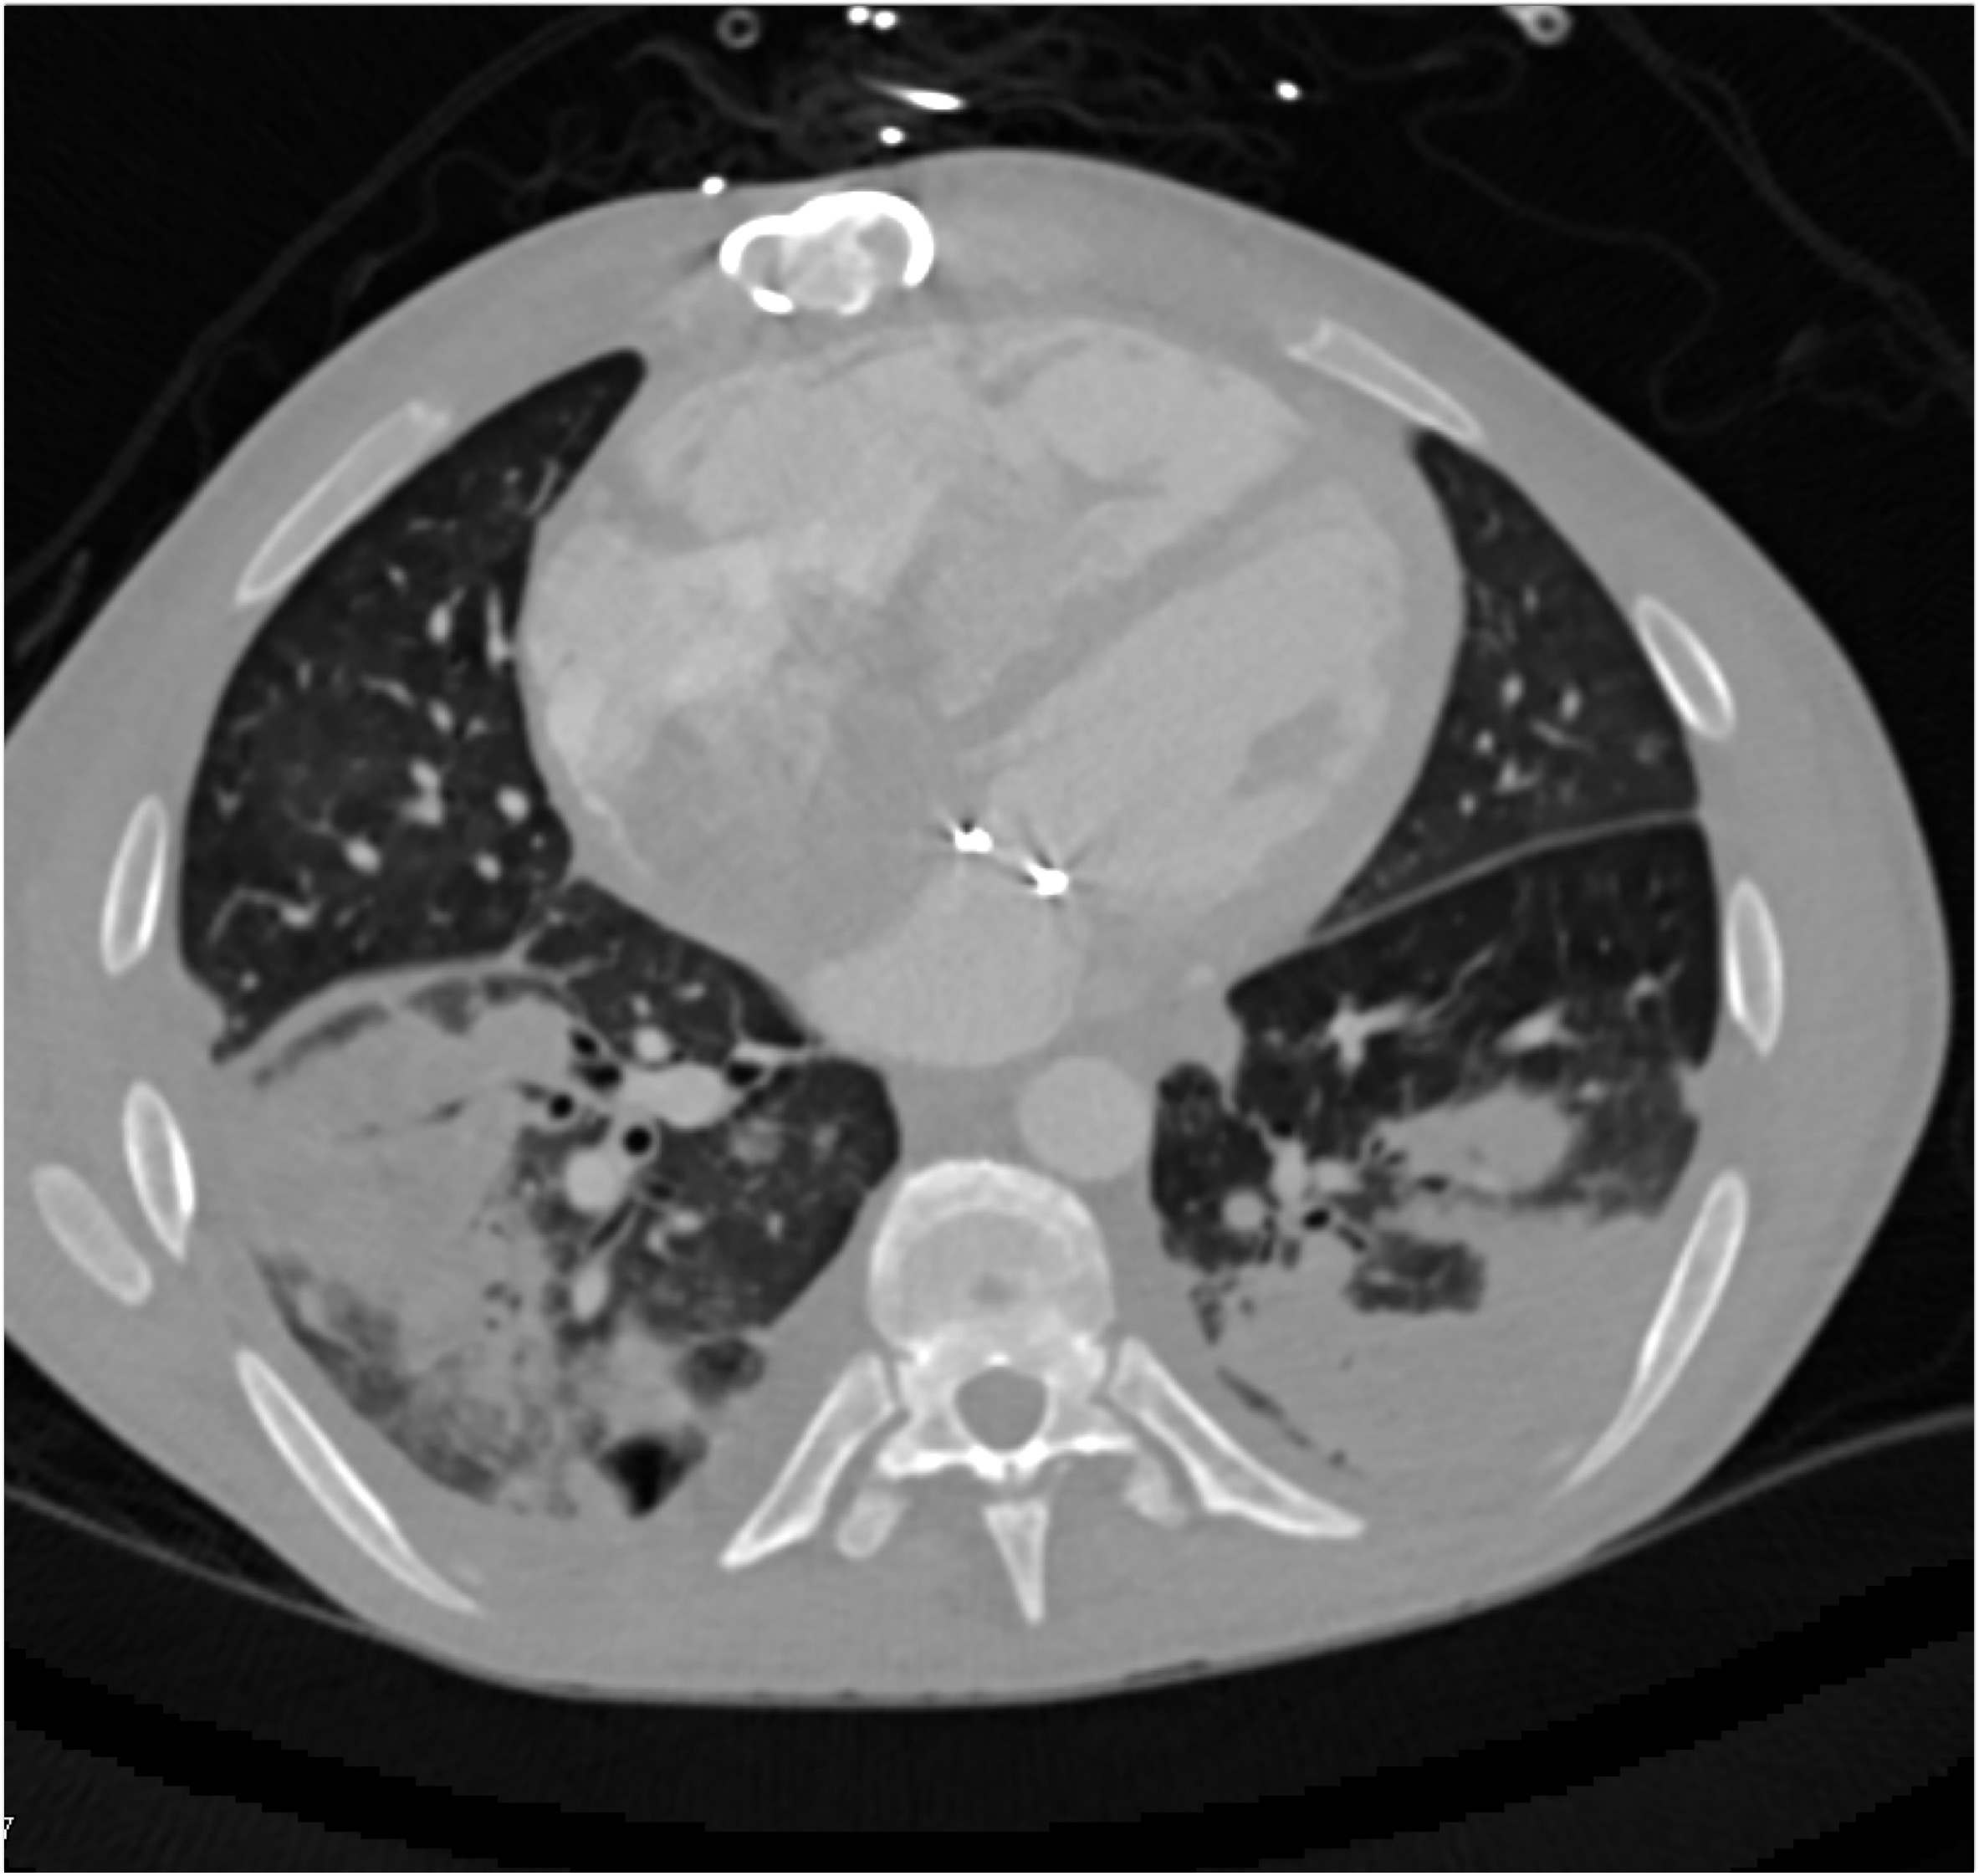

The most likely diagnosis in this case is?

vegetations in pulmonary valve

failed pulmonic valve

normal appearance of repaired pulmonary valve

abscess of the pulmonary artery